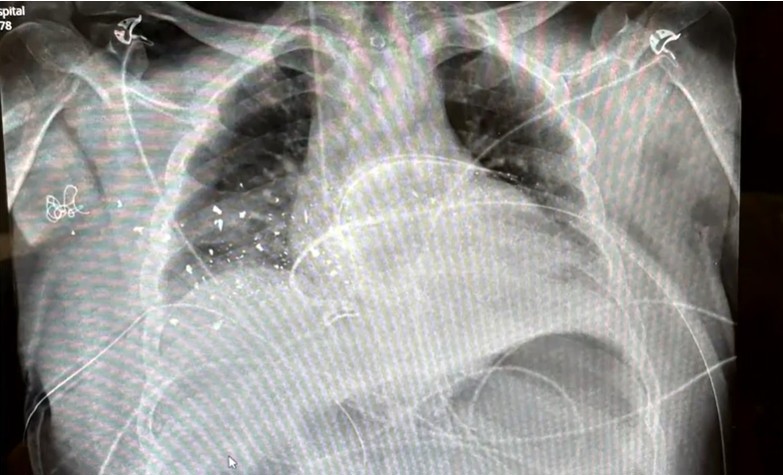

Rabbi Yanky Super's chest x-ray

He was shot in the chest and back, which left his body peppered with bullet fragments.